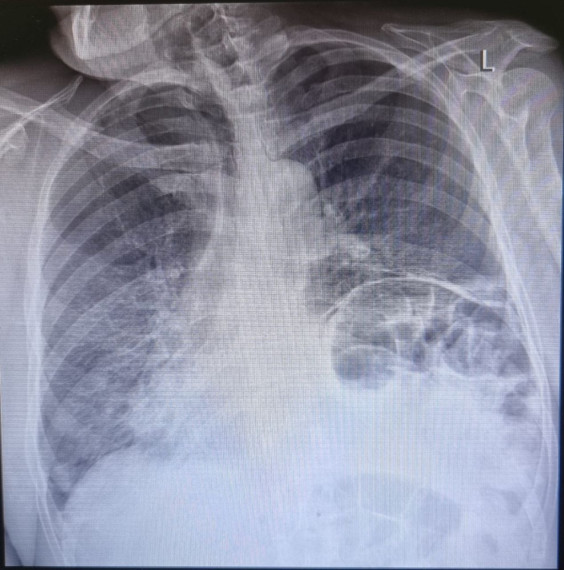

Сложная операция в Усинской ЦРБ вернула пациента к активной жизни

Операцию выполнила слаженная бригада в составе хирургов Александра Петрова и Шахбоза Абдихакимова, анестезиолога-реаниматолога Сергея Бородия и среднего медицинского персонала. После операции пациент демонстрирует положительную динамику.

Проведенное хирургическое вмешательство высшей категории сложности позволило и устранить угрозу жизни пациента, и создать условия для полного восстановления его физических возможностей. Это соответствует ключевым задачам национального проекта "Активная и продолжительная жизнь", направленным на сохранение трудоспособности и улучшение качества жизни граждан.